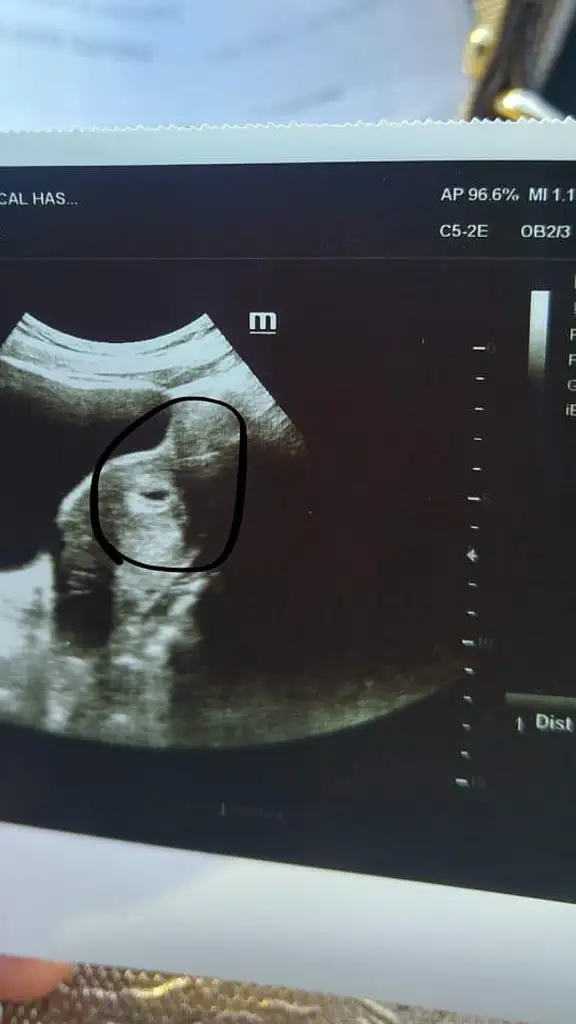

Kesemiz bu canmMaşallah arkadaşım cinsiyet tahmini yapıyor da yuvarlaksa erkek fasulye gibi ise kızmış

Arkadaşımın teorisine göre bir prenses gelecek sanırımKesemiz bu canm![]()